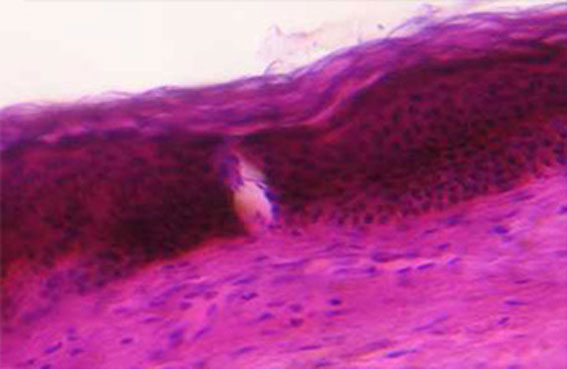

运用其特殊的治疗头把一个大的光斑分割成点状光斑,在真皮层进行一个磨削形成一个微创,胶原纤维开始重新排列,同时可以破坏增生的毛细血管,松解真皮层疤痕,真正形成了非剥脱祛疤。